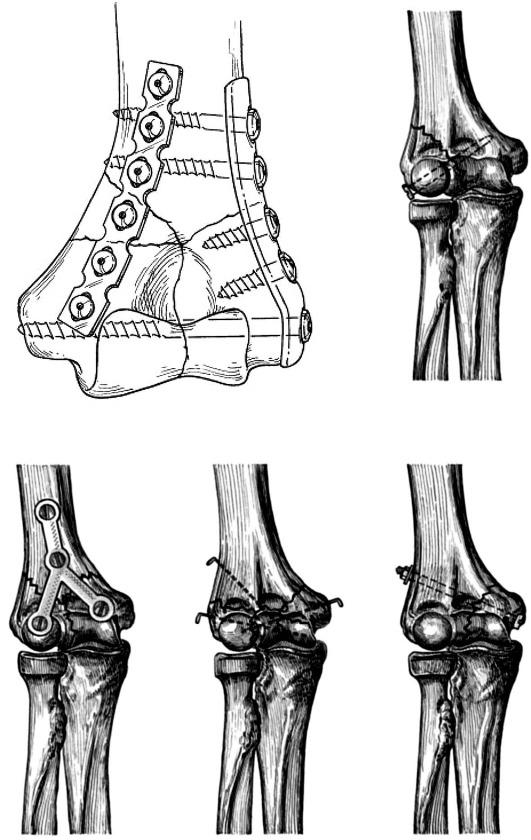

В БНИЦТО в период с 2008 по 2015 гг. произведено оперативное лечение 42 больных со сложными внутрисуставными переломами дистального отдела плечевой кости. Возраст больных варьирует от 21 до 52 лет. Подбирали больных с открытыми и закрытыми переломами типа C 1, 3 по классификации АО /ASIF. Ключевые слова: накостная пластина, остеосинтез, плечевая кость, ЛФК, реабилитация.

Материалы и методы исследования: В БНИЦТО период с 2008 по 2015 гг. в произведено оперативное лечение 42 больным со сложными внутрисуставными переломами дистального отдела плечевой кости. Возраст больных варьирует от 21 до 52 лет. Подбирали больных с открытыми и закрытыми переломами типа О 1, 3 по классификации АО / Л8№.

Методика реабилитации: Мы считаем, что самым главным моментом при лечении больных со сложными внутрисуставными переломами дистального отдела плечевой кости является раннее начало движений в локтевом суставе.

Результаты и обсуждение: Анатомически точная репозиция и стабильная фиксация костных отломков, позволяет практически полностью отказаться от внешней иммобилизации и приступить к ранней разработке сустава. Мы, считаем, что немаловажную роль в восстановлении функции сустава играет правильное ведение больных в период реабилитации. Тем самым снижаются сроки временной нетрудоспособности, и обеспечивается достижение хороших функциональных результатов.

Переломы дистального отдела плечевой кости (локтя) возникают в результате падения на локоть с согнутой рукой.Выделяют две основные группы: те, которые затрагивают поверхность сустава (внутрисуставные переломы), и те, которые не затрагивают поверхность сустава (внесуставные переломы). Кроме того, лечение этих переломов у детей отличается от лечения у взрослых. В большинстве случаев эти переломы нестабильны и требуют какой-либо внутренней фиксации, чтобы предотвратить их заживление в плохом положении.

Переломы дистального отдела плечевой кости у взрослых обычно требуют хирургического вмешательства. Небольшой процент этих переломов можно вылечить с помощью гипсовой повязки на руку. Однако длительная иммобилизация локтя приводит к значительной и длительной скованности сустава. Эти переломы обычно затрагивают поверхность сустава (хрящ). Обычно поверхность сустава гладкая, что позволяет костям скользить друг относительно друга с очень небольшим трением.Если поверхность неконгруэнтна, потому что кости не выровнены, происходит хроническое повреждение сустава, что в конечном итоге приводит к артриту. Очень важно убедиться, что поверхность хряща восстанавливается как можно точнее. Операция рекомендуется при смещении поверхности сустава на 2 мм или более.

Хирургия включает повторное выравнивание перелома и проведение ремонта пластинами и винтами. Операция длится около 2 часов, и большинство пациентов остаются в больнице на ночь.Наиболее частыми осложнениями операции являются инфекция (около 2%), ригидность (10%) и повреждение нервов, называемое нейропраксией (около 2-3%). Нейропраксия — это состояние, при котором нерв ((локтевой нерв)), проходящий вдоль задней части локтя (забавная кость), раздражается и не работает должным образом после операции. В большинстве случаев это временно, но на устранение может уйти несколько месяцев. После хирургического вмешательства пациенты могут начать двигать рукой в течение 2 недель после операции, и риск долговременной скованности уменьшается.